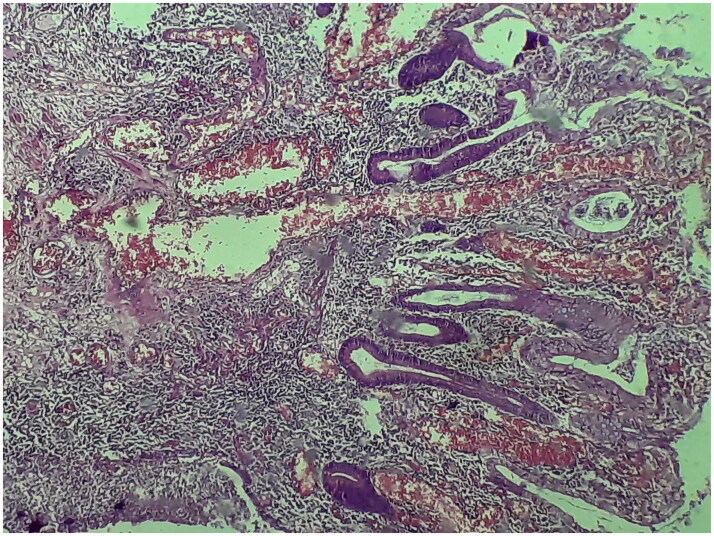

Lichen Planus is an inflammatory skin disease that has been reported to be associated with inflammatory diseases like Inflammatory Bowel Disease or with medication use such as sulfasalazine. We report a case of lichen planus in a 62-year-old patient with ulcerative colitis receiving sulfasalazine. Within three years of treatment, the patient developed an erythematous rash on her forehead and wrists, which gradually worsened and spread to her arms, forearms, neck, and upper back. Lichen planus was suspected and later confirmed through histopathological examination. Consequently, sulfasalazine was discontinued, leading to partial resolution of the skin lesions. Our case highlights the importance of a thorough patient interview, as the timeline of skin lesions in relation to medication use and disease activity.